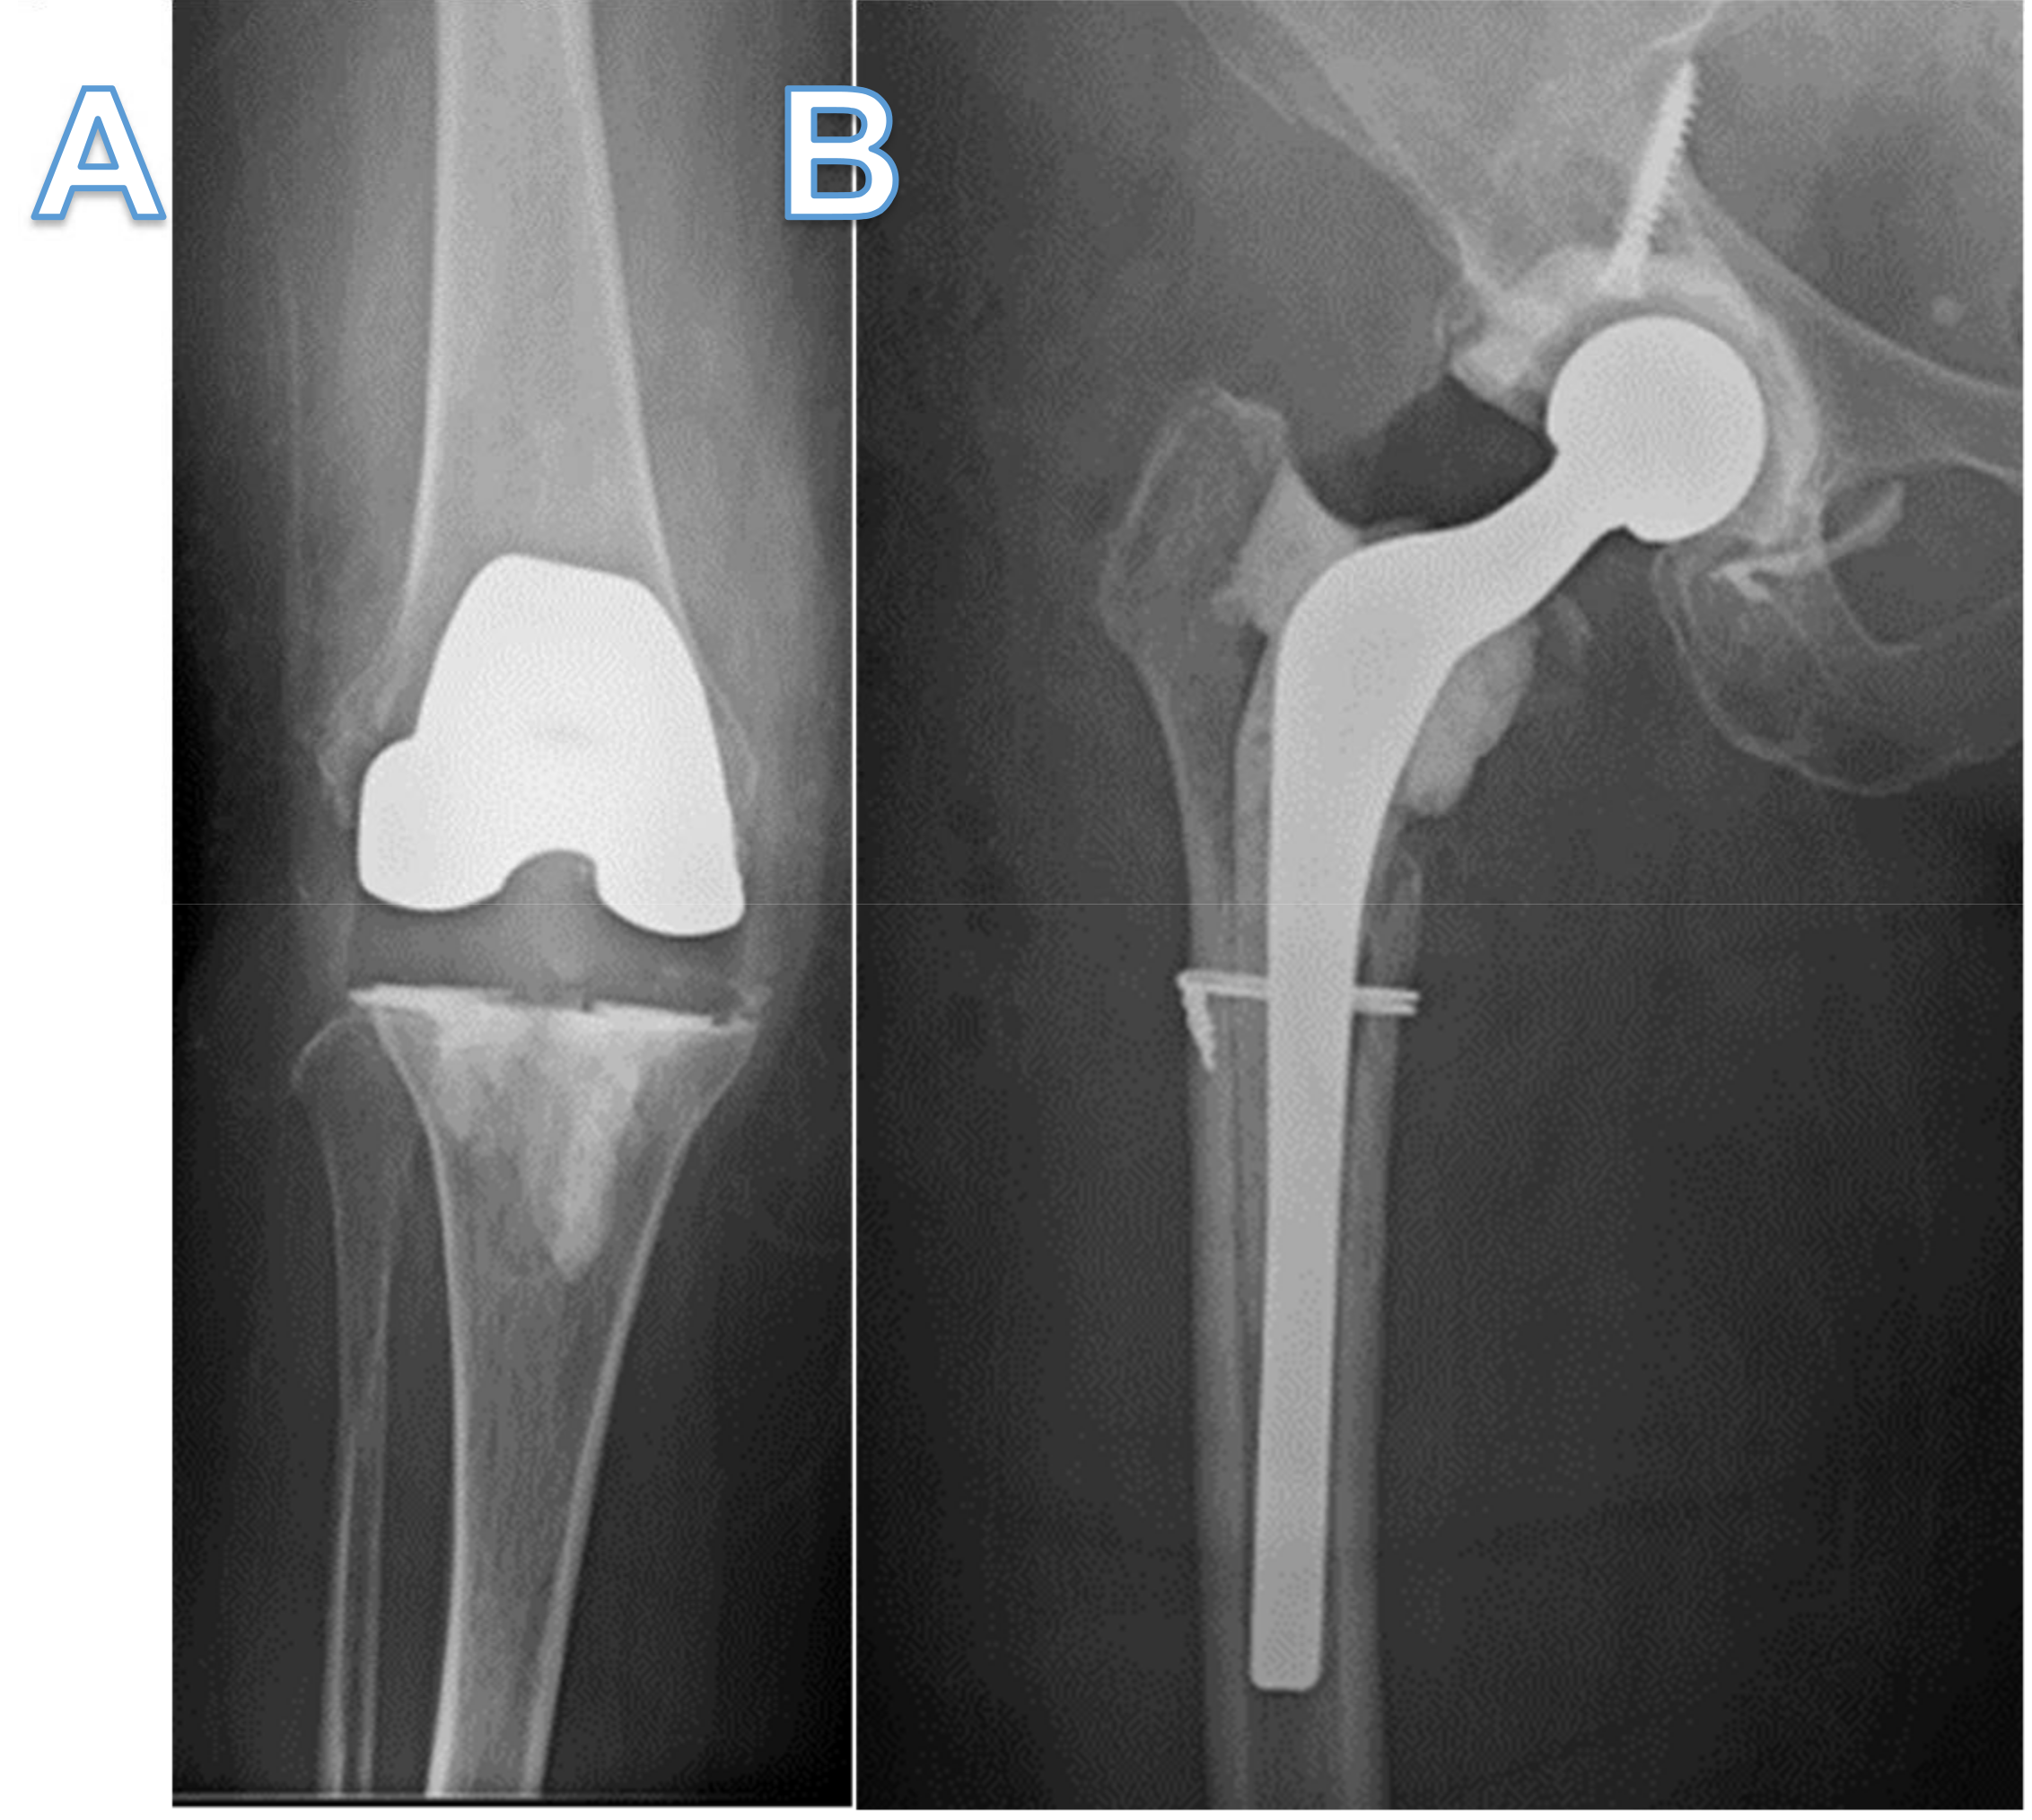

Arthrocentesis of her knee grew MRSA, prompting revision surgery with explant of prosthesis and insertion of a temporary implant with high dose vancomycin and tobramycin-loaded cement (Figure 1A). Despite being treated with vancomycin, she developed right hip pain in which a subsequent arthrocentesis grew MRSA. She then underwent DAIR of the right hip and was discharged on IV daptomycin 500 mg daily and oral rifampin 600 mg daily, but rifampin was later discontinued 7 days later due to intolerance.

Figure 1.

X-ray of knee and hip before and after bacteriophage therapy. (A,B) X-ray anterior-posterior view of right knee and hip showing temporary antibiotic-coated knee prosthetic and Prostalac hip spacer with residual cerclage wire and screw. (C,D) X-ray lateral view knee and anterior-posterior view hip showing total knee and hip arthroplasties implanted after bacteriophage therapy and subsequent proven sterility of the joints. Retained cerclage wire still present.

Her right hip pain, swelling and erythema recurred while on daptomycin, prompting a two-stage revision with insertion of an antibiotic-loaded PROSTALAC (Depuy-Synthes, Warsaw, IN, USA) hip spacer (Figure 1B). She was then treated with daptomycin 500 mg daily for another six weeks, after which antibiotics were stopped. Two weeks after stopping antibiotics, she presented again with right knee pain, swelling, erythema and systemic signs of sepsis. An arthrocentesis culture grew MRSA. Due to hemodynamic instability, she first had irrigation and debridement of the knee, followed by an exchange of the antibiotic-impregnated temporary knee prosthetic to a new one four days later. Given the refractory nature of her infection, two Hickman catheters were inserted for intra-articular vancomycin dosing. She was then restarted on IV daptomycin as well as twice-daily intra-articular vancomycin. Transesophageal echocardiogram was negative for endocarditis, and computed tomography (CT) of the chest, abdomen and pelvis did not reveal any other foci of infection.

Two months thereafter, she underwent a permanent total hip arthroplasty with adjuvant intra-articular bacteriophage therapy (1.2 × 109 PFU/mL), diluted in 10 mL of normal saline (Figure 1C). Five milliliters (2.4 × 108 PFU/mL) were injected into the femoral canal prior to implantation of the permanent femoral component, and the remaining 5 mL (2.4 × 108 PFU/mL) were injected into the joint prior to closure. All intraoperative bacteriological cultures were negative. Three months later, while still off antibiotics, she underwent permanent total knee arthroplasty with intraoperative bacteriophage therapy (1.2 × 109 PFU/mL) diluted in 10 mL of normal saline (Figure 1D). The bacteriophage dose was divided with 3 mL (4 × 108 PFU/mL), injected into the femoral canal, and 3 mL (4 × 108 PFU/mL) injected into the tibial canal prior to implantation of the components. The remaining 4 mL (3 × 108 PFU/mL) was injected into the joint prior to closure. All intraoperative bacteriological cultures were negative. Eleven months since receiving the first doses of personalized bacteriophage therapy, there has been no evidence of recurrence, and the patient is ambulating without a cane, able to climb stairs and driving using her operative right leg.